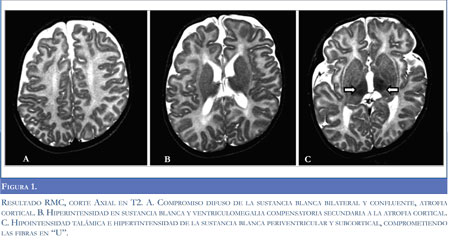

En la figura 1 se observan los resultados de la Resonancia Magnética Nuclear.

La presencia de leucoencefalopatía difusa, con atrofia cortical y compromiso talámico observado en las imágenes de RMN es compatible con lo reportado en la literatura para gangliosidosis GM1 (7,8); estos hallazgos aunados a la historia clínica que sugerían una enfermedad neurodegenerativa y confirmación bioquímica de la deficiencia en la actividad de la beta-galactosidasa establecen el diagnóstico definitivo del paciente. Teniendo en cuenta el cuadro clínico y edad de presentación, se considera una variante juvenil o tipo II de gangliosidosis GM1. Los hallazgos de esta forma de presentación clínica son variables; los más frecuentemente reportados son retardo en el neurodesarrollo (96%), anormalidades esqueléticas (69%), facies toscas (66%), hipotonía (50%), epilepsia (18%) e hipertonía (4%) (1,6).